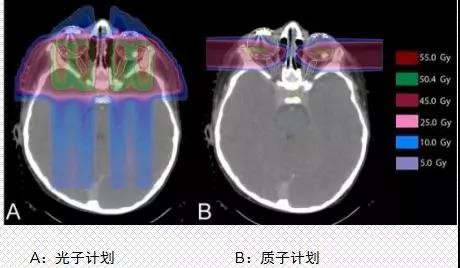

第二大优势是质子的辐射可以最大限度降低对正常组织的伤害,对目标肿瘤细胞造成最大的损害。以儿童髓母细胞瘤为例,我们可以看到普通放疗产生的大部分副作用,质子都完美的规避了。

第三大优势是质子治疗可以降低二次肿瘤的发病率。以头颈肿瘤为例,常规放疗比质子治疗的辐射剂量高出25Gy,这意味什么呢?25Gy=你做了12500头颈CT,增加96%罹患二次肿瘤的风险!